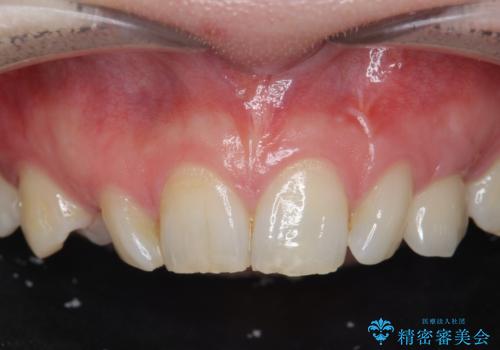

骨造成を伴う 前歯部インプラント治療

前歯のインプラント治療は骨量・歯肉の厚み・インプラントの方向をしっかりと計画することで、審美的で長持ちを期待できるような仕上がりとなります。